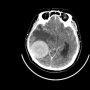

في إنجاز علمي جديد قد يمثل بداية ثورة في علاج أمراض الدماغ التنكسية مثل ألزهايمر، طوّر فريق من علماء جامعة كاليفورنيا في إيرفين تقنية مبتكرة تعتمد على الخلايا الجذعية لعلاج أمراض الدماغ. الفريق نجح في تطوير خلايا مناعية دماغية تُعرف بـ"الخلايا الدبقية الصغيرة"، وهي قادرة على تتبع السموم المتراكمة في الدماغ والتخلص منها، مما يساعد على استعادة وظائف الدماغ والذاكرة لدى الفئران.

تمكن الفريق من تحويل الخلايا الجذعية إلى خلايا دبقية صغيرة باستخدام تقنية كريسبر لتعديل الجينات. وهذه الخلايا المعدلة تقوم بإفراز إنزيم نيبريليسين الذي يساعد في تفكيك اللويحات السامة في الدماغ فقط عند الحاجة، مما يقلل من تأثيرها الضار على الأنسجة السليمة ويحد من الالتهابات العصبية.

النتائج الأولية لهذه التقنية كانت مبشرة للغاية، حيث لاحظ الباحثون تحسنًا ملحوظًا في أداء الدماغ والذاكرة لدى الفئران التي خضعت للعلاج، مما يفتح أفقًا جديدًا لعلاج الأمراض العصبية التنكسية مثل ألزهايمر، وربما أيضًا التصلب اللويحي وسرطان الدماغ.